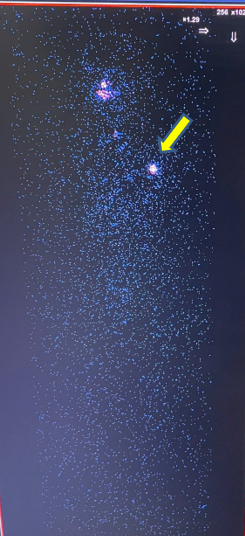

- Chụp xạ hình toàn thân với I-131 liều 5 mCi:

Tại vị trí tuyến giáp tập trung hoạt độ phóng xạ ngang mức phông.

Trên xạ hình toàn thân có 1 điểm bắt xạ bất thường tại vị trí vùng ngực trái.

Hình 4. Hình ảnh xạ hình toàn thân với I-131.

Hình 5. Hình ảnh xạ hình toàn thân sau điều trị I-131: tăng hoạt độ phóng xạ tại vùng ngực trái (mũi tên vàng).